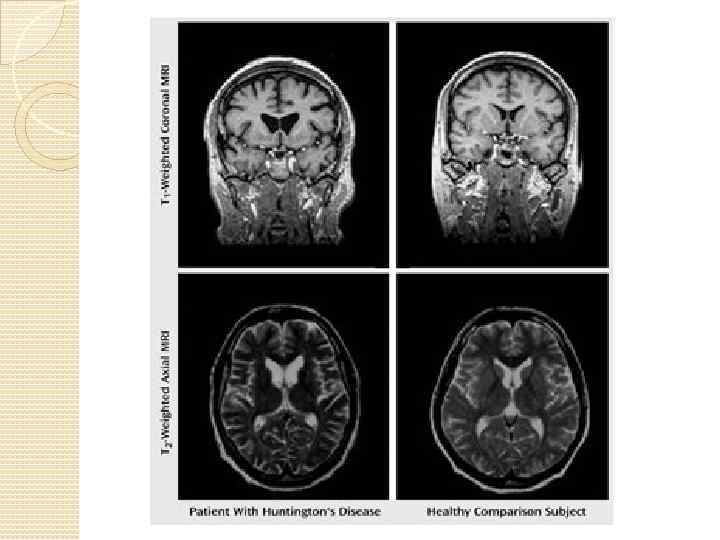

Поражения на клеточном и организменном уровне: Поражает стриатум, кору ГМ, гиппокапм, клетки Пуркинье в Поражения на клеточном и организменном уровне: Поражает стриатум, кору ГМ, гиппокапм, клетки Пуркинье в мозжечке

Повреждение базальных ганглиев ведет к : Затруднению начала движения Непроизвольной инициации движений Беспорядочным движениям Повреждение базальных ганглиев ведет к : Затруднению начала движения Непроизвольной инициации движений Беспорядочным движениям